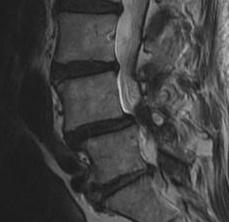

MRI

Demonstrate stenosis with spondylolithesis